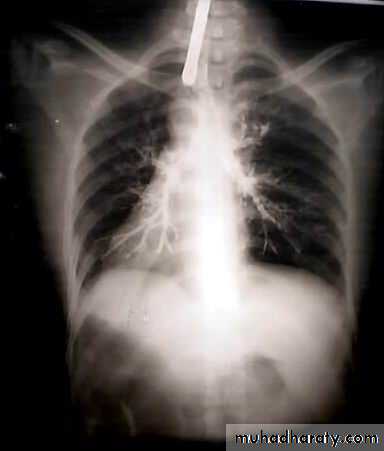

• Chest X-ray ,CT chest ..

• Signs of inoperability :-1-Bloody pleural effusion .positive for malignant cells2-Horner’s syndrome .3-Vocal cord paralysis4-Phrenic nerve palsy(elevated hemi diaphragm)5-SVC obstruction 6-Distant metastasis 7-If during surgery ,the tumor locally spreading or cannot be remover technically or fixed to the PA or to the heart ,it is technically irresectable

• Treatment 1-Surgery more than 50%of the patients have distant metastases at the time of diagnosis .50% Iresectable per operatively15-20 % resectability rate Surgery ..segmentecomy , lobectomy . pneumectomy